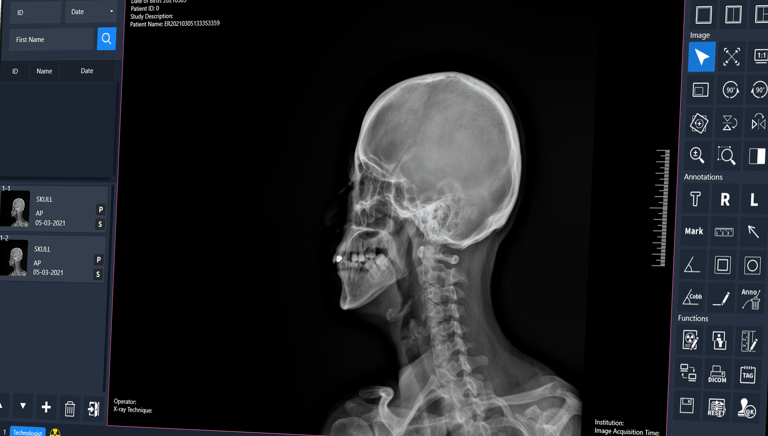

Acceso Seguro y Rápido a tus Imágenes Médicas

En LinkMedic llevamos la radiología al siguiente nivel con nuestro sistema PACS en la nube. Procesa, comparte y almacena radiografías digitales de forma eficiente y sin límites geográficos. Garantizamos acceso seguro, imágenes de alta calidad y una experiencia ágil que optimiza tu flujo de trabajo, mejorando la atención de tus pacientes en cualquier momento y lugar.

PACS DE EXAMVUE

EXAMVUE DUO ACQUISITION SOFTWARE